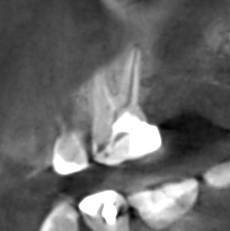

Александр В.В. Опубликовано 29 марта, 2023 Поделиться Опубликовано 29 марта, 2023 (изменено) Здравствуйте! Уже давно на шестом верхнем зубе есть гранулёма или киста размером 5-6 мм. Несколько лет назад пробовали класть кальций в каком-то виде, но, видимо, не помогло. Сейчас всё-таки решил перелечить этот канал, но эндодонтист сказал, что это только часть дела и надо делать все каналы. Кроме того, как я понял, проблема не в том канале, который запломбирован, а в том, который проходит рядом с ним и не был обнаружен и запломбирован. На этом снимке это верхний левый корень и в его правой части темное пятно - это вроде и есть тот ненайденный канал. Здесь видна гранулёма и запломбированный канал (корень слева). А здесь справа от запломбированного канала (левого корня), тот самый незапломбированный. Но у меня есть сомнения по поводу такого вывода, потому что в других каналах можно обнаружить более очевидные "темные каналы" в зависимости от среза. На этих снимках обращаю ваше внимание на правый канал. Если нужно, могу предоставить другие проекции, потому что имею диск с данными КЛКТ. Вопросы. 1. Действительно ли на снимке ненайденный канал на корне зуба с гранулёмой? 2. Возможно ли перелечивание одного канала с гранулёмой или кистой или нужно распломбировать сразу все каналы во всех корнях? 3. Если на снимке всё-таки ненайденный канал, то не кажется ли вам, что он прямой, а не изогнутый? Если прямой, его может обработать терапевт без использования микроскопа? Изменено 29 марта, 2023 пользователем Александр В.В. Ссылка на комментарий

Александр В.В. Опубликовано 16 декабря, 2023 Автор Поделиться Опубликовано 16 декабря, 2023 Здравствуйте! Провёл лечение этого зуба, а гранулёма и боли остались. Прошу совета. Рассказываю по порядку. 1. До перелечивания этого зуба (шестнадцатый) были постоянные воспаления десны из-за разрушенной коронки зуба и неровных краёв пломбы в поддесневой части со стороны отсутствующего соседнего зуба. Также были боли при прикосновении пальцем десны в проекции корней зуба со стороны щеки, то есть, примерно там, где находится гранулёма. При этом припухлости этой области я не замечал. 2. На первом этапе лечения были рассверлены каналы, в том числе и ранее не найденный, и на 7 дней заложен препарат для растворения остатков пломбировочного материала. Также была установлена временная пломба. Уже после первого посещения я заметил, что ушла боль при прикосновении пальцем проекции корней. Но 2-3 дня периодически происходило выделение бурой жидкости из носа в виде капель при наклоне головы. Зуб не болел, ничего не опухало. 3. На втором этапе были удалены остатки пломбировочного материала из корней, заложен препарат кальция для «лечения» и снова установлена временная пломба. Точно не знаю, для чего применяется кальций. То ли как антисептическое средство, то ли для восстановления костной ткани. Опять несколько дней наблюдалось выделение жидкости из носа. Болей не было три недели ни в области проекции корней, ни десны со стороны отсутствующего зуба, а потом опять начала болеть десна скорее всего из-за разрушения временной пломбы. С кальцием ходил 30 дней. 4. На третьем этапе были запломбированы все каналы, установлен стекловолоконный штифт и восстановлена коронка зуба с помощью пломбировочного материала, но при этом зуб был выведен из прикуса. Стоматолог предупредил, что зуб может болеть 2 недели, как это бывает после пломбирования. На этот раз никаких выделений из носа не было. Болей или опухания тоже не было. Но примерно через 8 дней опять начала болеть десна, как со стороны отсутствующего зуба, так и в проекции корней, причём, мне кажется, что даже сильнее, чем раньше. Возможно, это связано с тем, что я начал пытаться жевать этим зубом и более смело пользоваться зубной щёткой. Новые снимки зуба показали, что гранулёма осталась на своём месте. Вопросы. 1. Нормально ли то, что гранулёма осталась, несмотря на проведённое лечение? 2. На снимке потемнение десны справа от зуба – это воспаление? В чём может быть его причина? 3. Что появилось в пазухах? На снимках, сделанных год назад, этого не было. 4. Почему проходили боли на первых этапах лечения и появились снова после его окончания? 5. Что делать дальше? Ждать, что само пройдёт или принимать какие-то меры? Систематически таблетки не пил. Только однократный приём НПВС после каждого посещения стоматолога. Сейчас провожу полоскание зуба различными препаратами и мажу разными мазями и гелями для дёсен. Ссылка на комментарий